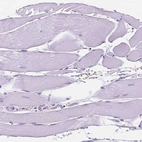

Immunohistochemical staining of human endometrium shows moderate membranous positivity in a subset of glandular cells.